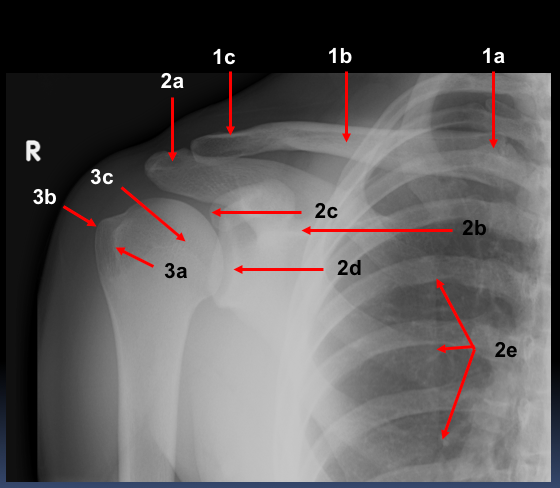

What are the labels?

1a - sternal end

1b - mid-shaft

1c - acromial end

2a - acromion

2b - spine

2c - coracoid process

2d - glenoid fossa

2e - medial border

3a - lesser tubercle

3b - greater tubercle

3c - head of humerus